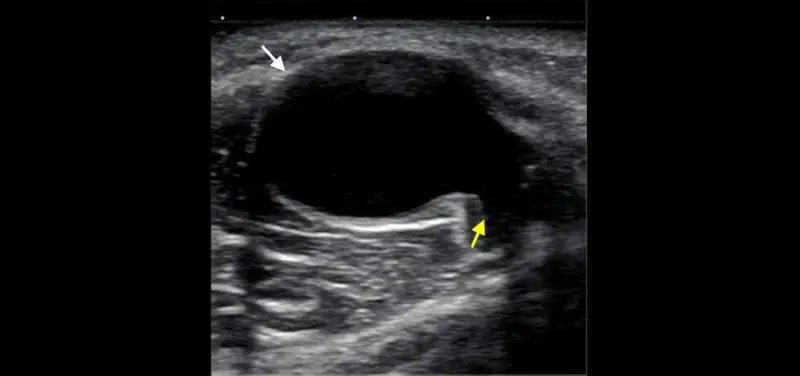

Image: Ultrasound obtained behind the knee of a young child with a soft bump shows a round cyst (white arrow) with a “tail” (yellow arrow) extending deep toward the joint between the muscles. This is a typical appearance and location for a benign cyst (also known as a Baker cyst at this location).